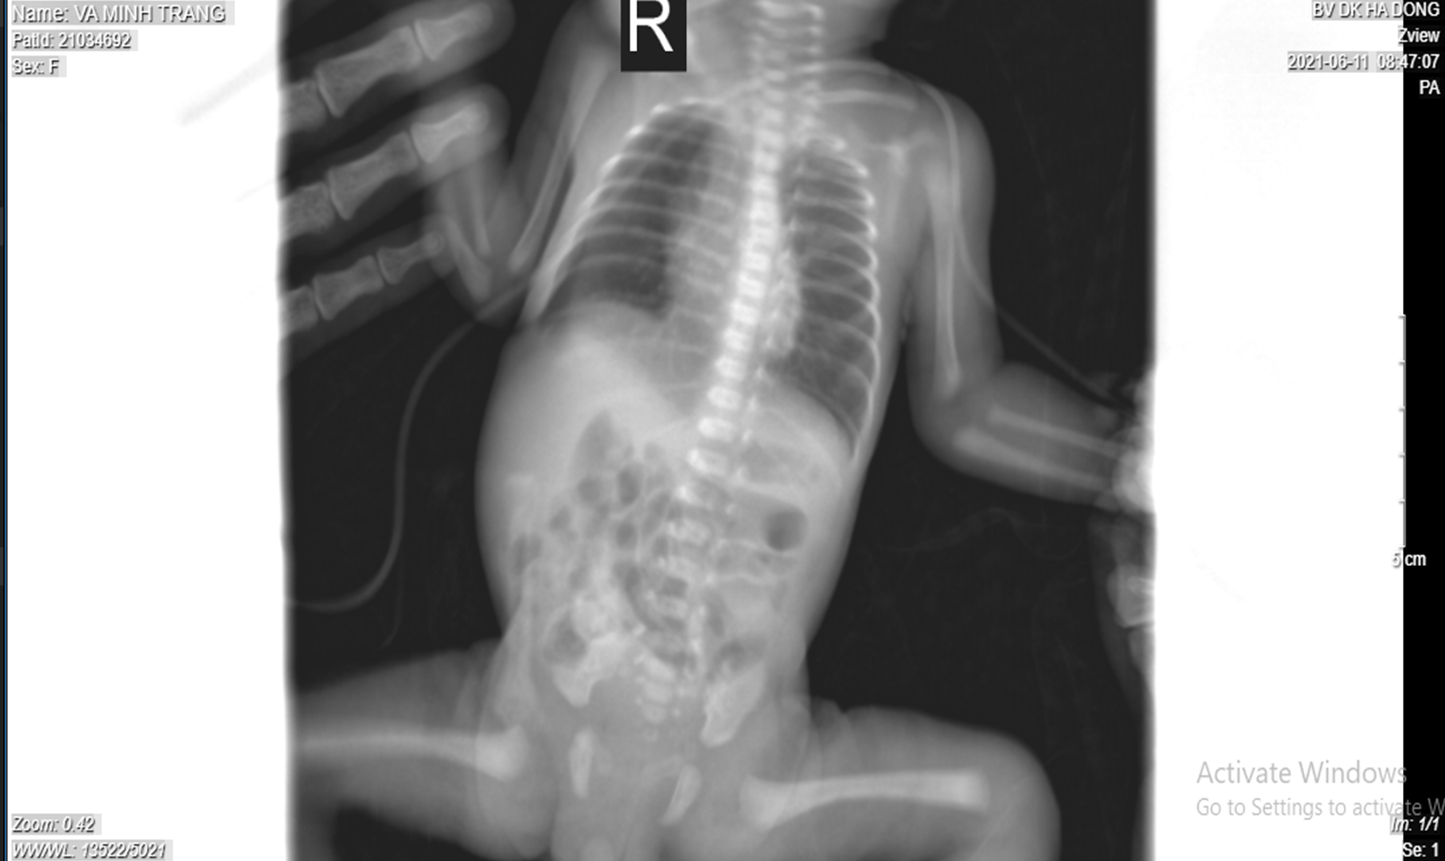

Sau bơm surfactant bằng phương pháp insure cho ca bệnh 30 tuần nặng 1200gr